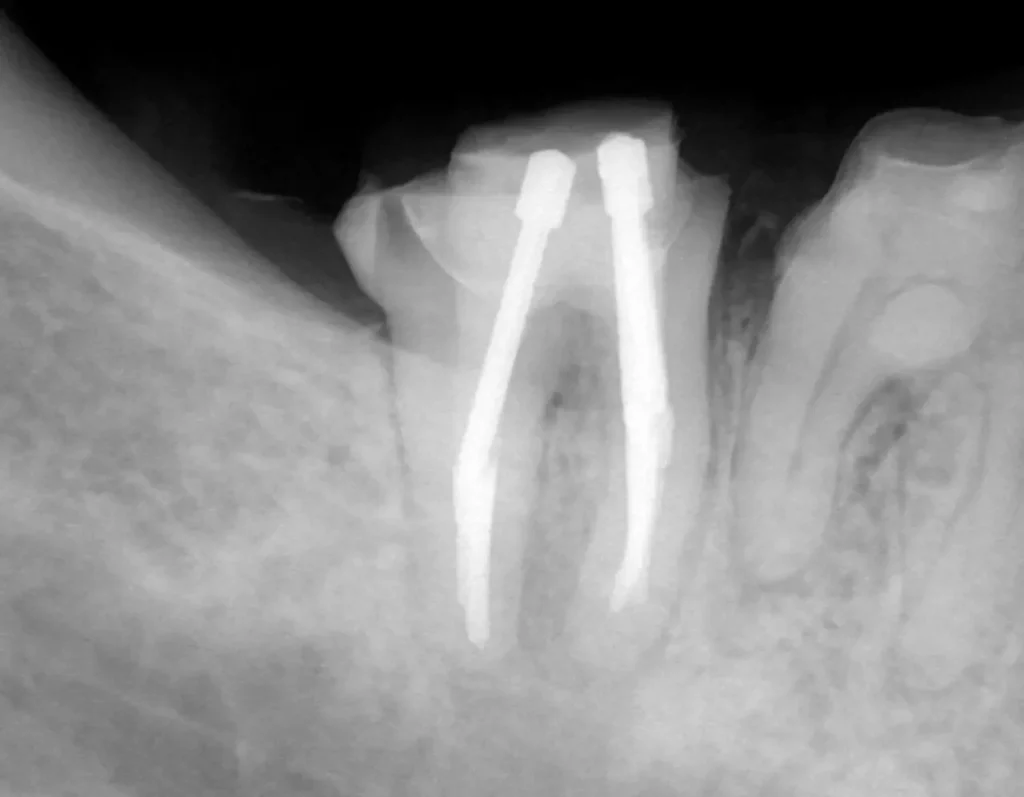

術中(ファイル試適)

レントゲン写真

ラバーダムシートを固定する金具が写っています、シートはバイ菌が

入らないように撮影時にも外しません